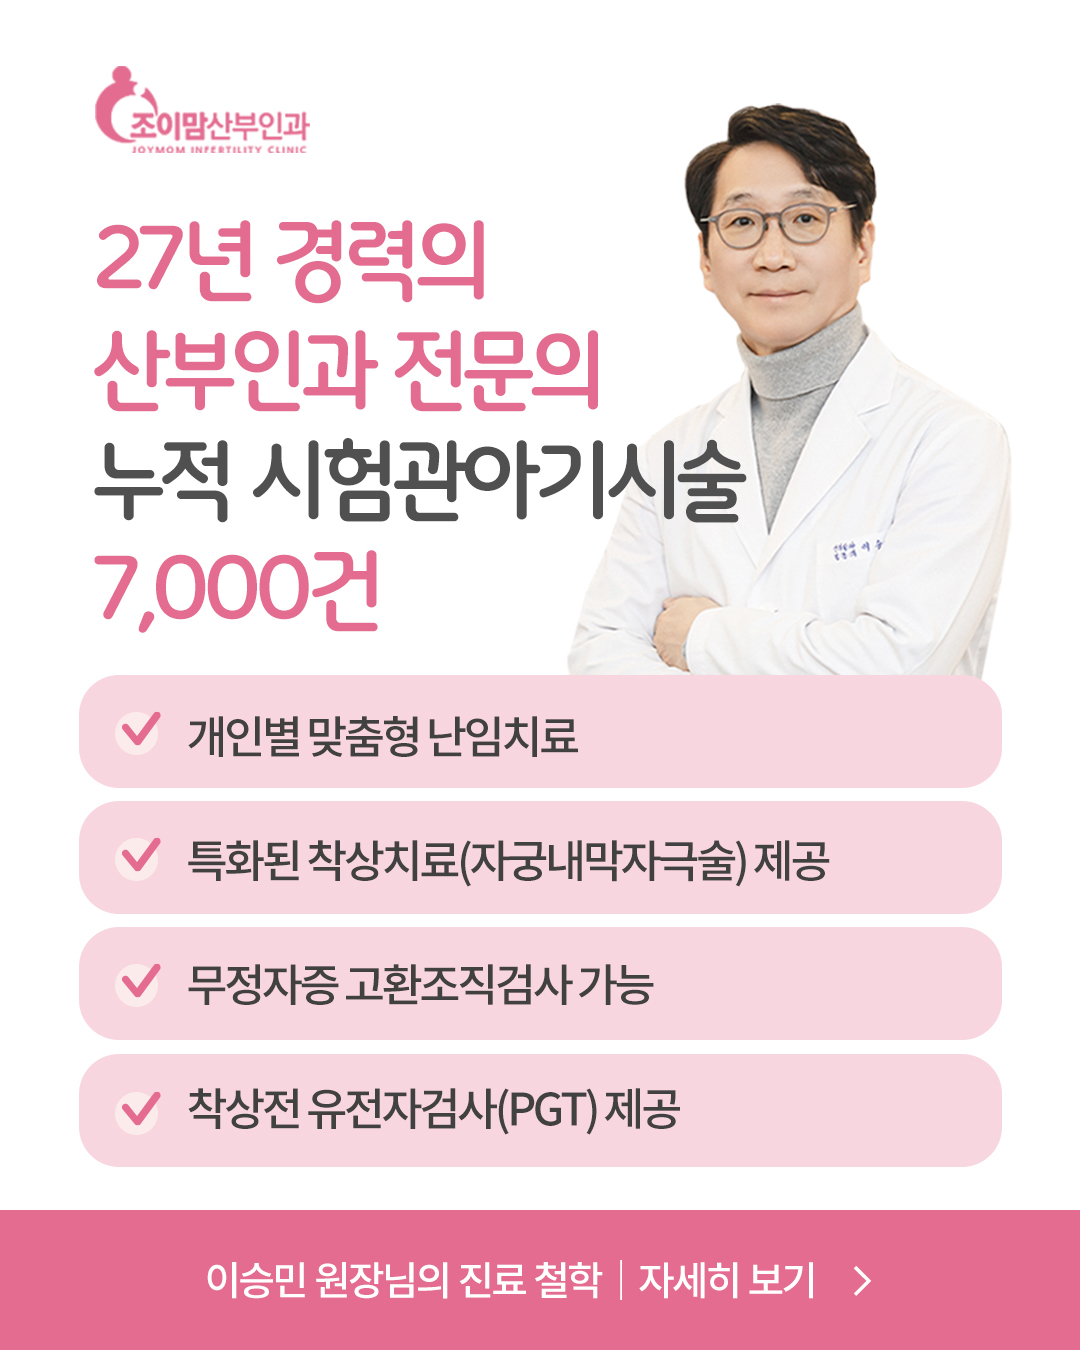

26년 이상 난임치료

경력의 대표원장

직접 진료 -

niPGT(차세대 비침습적

착상전 유전자검사) 가능 -

무정자증

(고환조직검사 가능) -